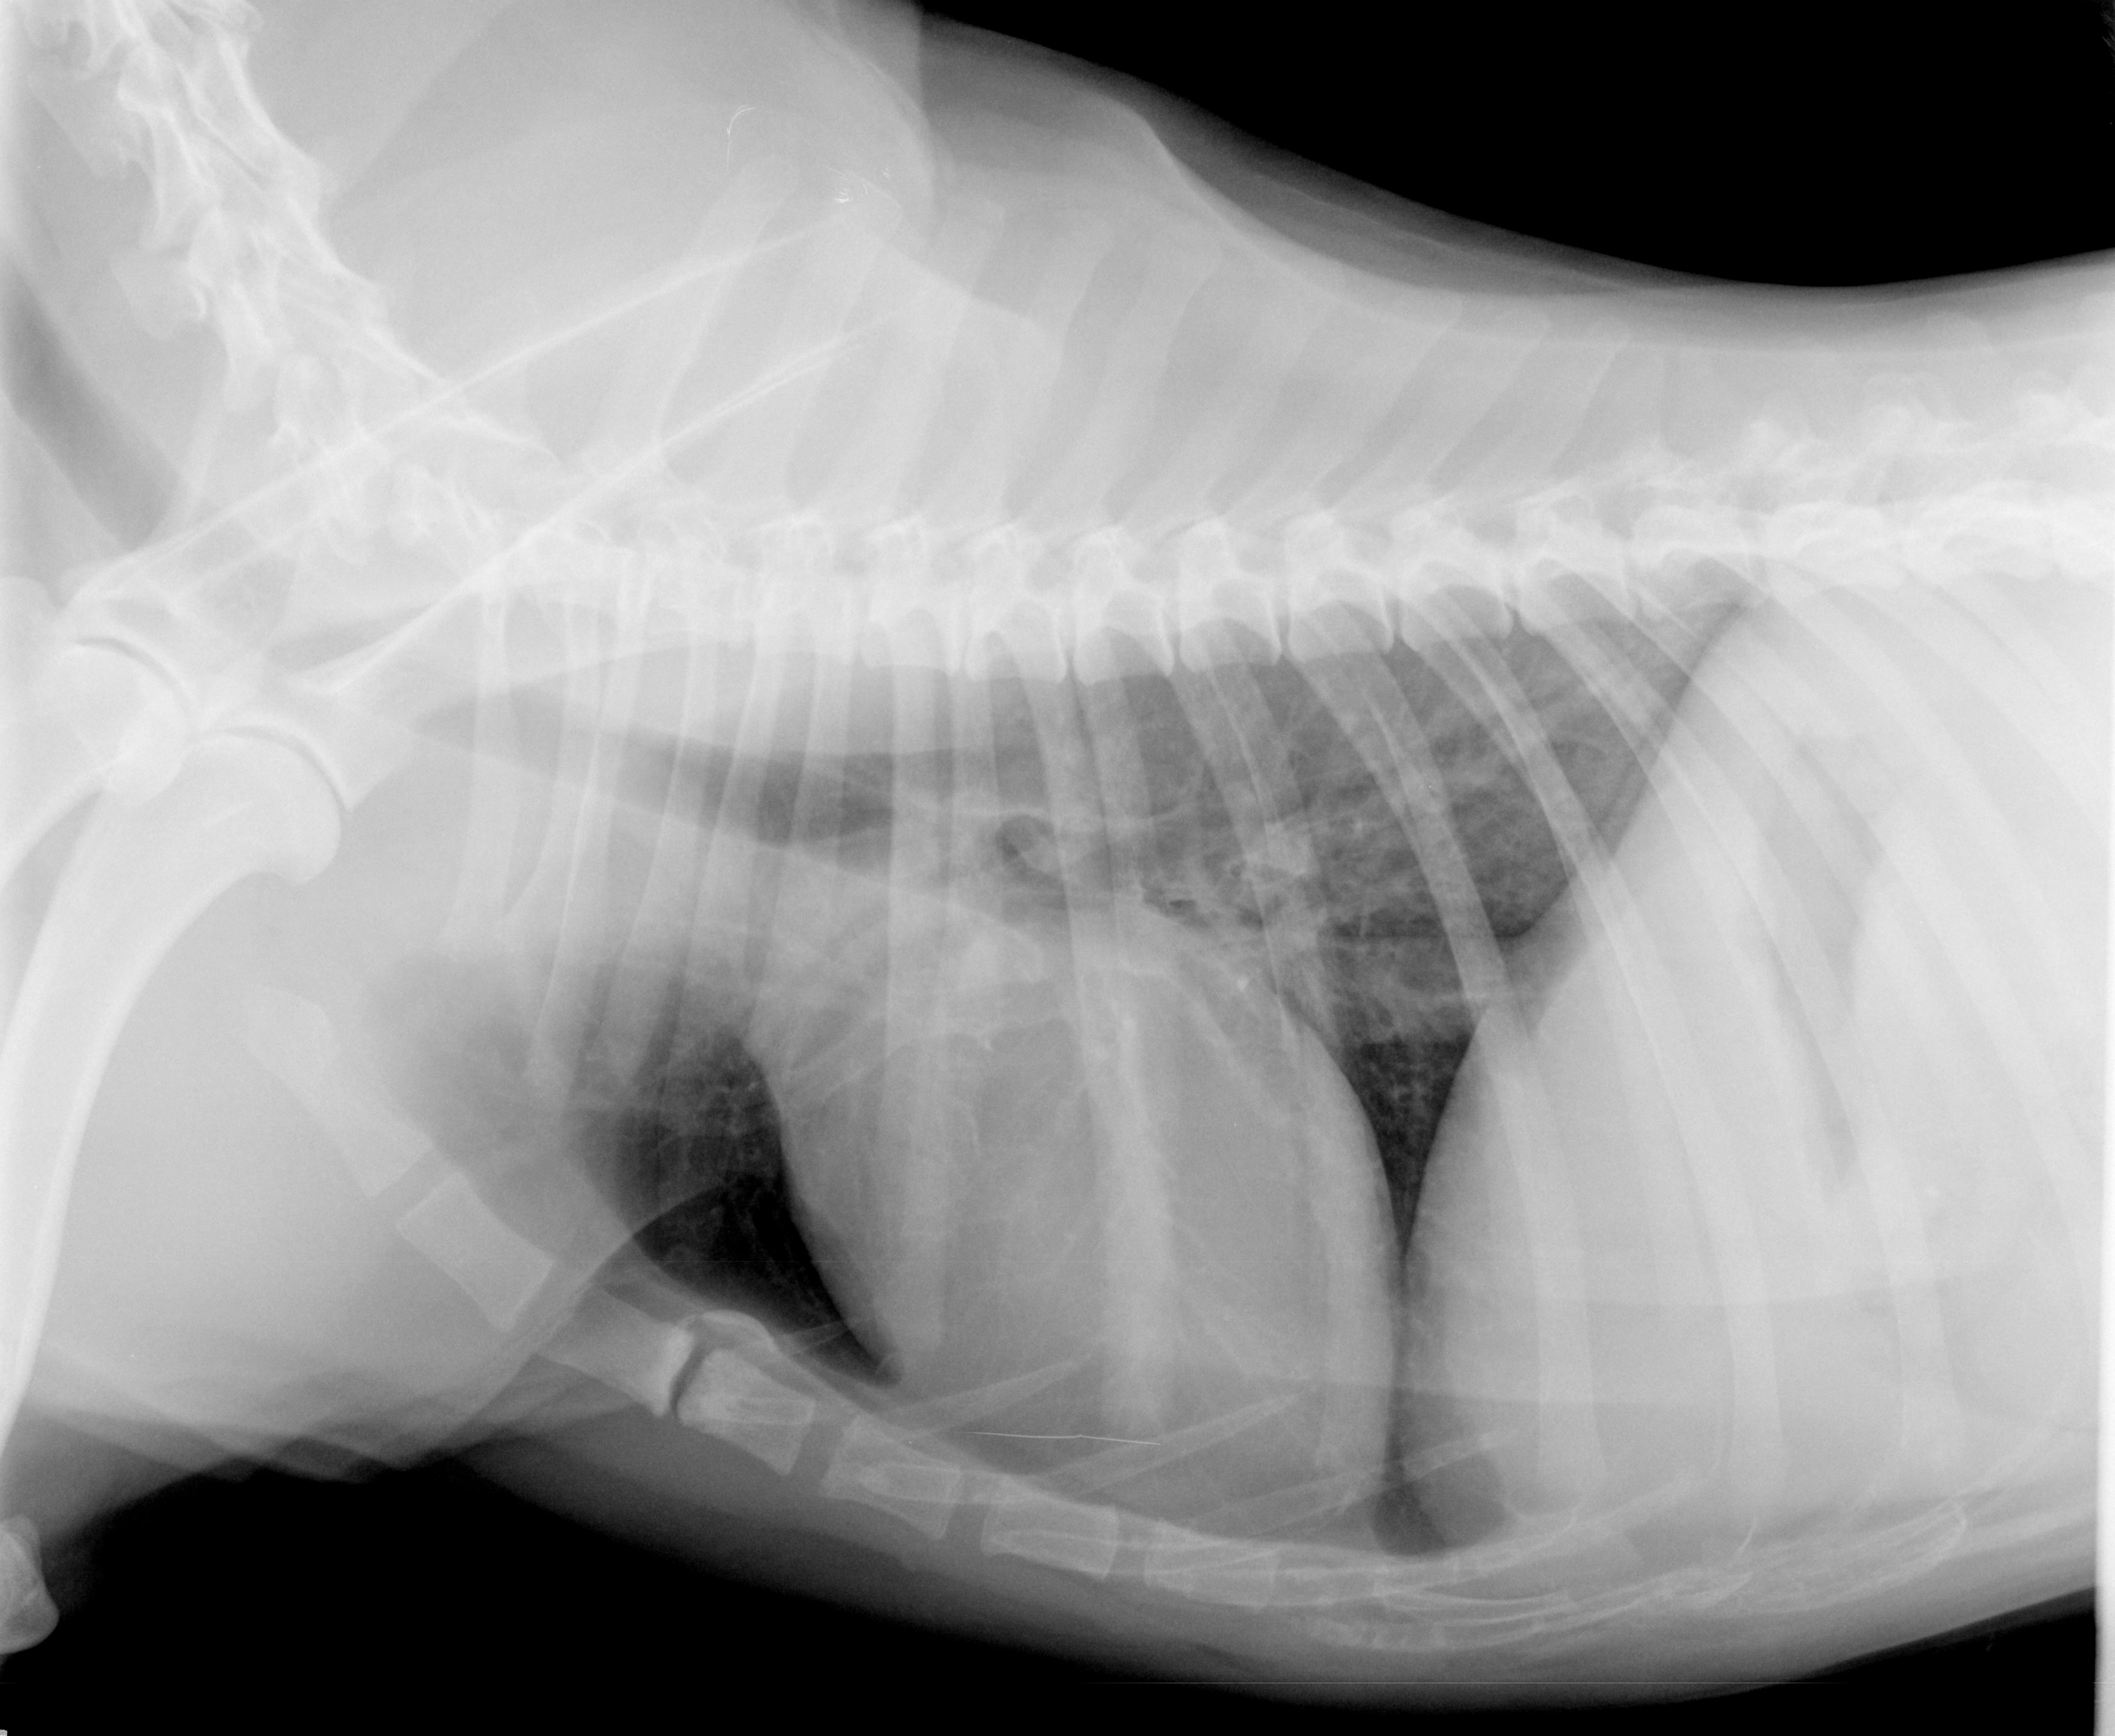

Der erste Schritt der weiterführenden Diagnostik war eine Blutuntersuchung. So können zum Beispiel ein niedriger Blutzucker oder Elektrolytverschiebungen zu Krampfanfällen führen. Wichtig ist auch die Ammoniak-Bestimmung. Vor allem bei sehr jungen Hunden kann eine angeborene Gefäßmissbildung (Lebershunt) zu Krampfanfällen führen. Dabei umgeht das Blut aus dem Darm das Lebergewebe und wird durch ein Gefäß („Shunt“) direkt zur Hauptvene geleitet. Dadurch kann das Blut in der Leber nicht „entgiftet“ werden und die Giftstoffe gelangen in das Gehirn und können zu Krampfanfällen führen. Einer dieser giftigen Stoffe ist Ammoniak, dessen Bestimmung eine schnelle Beurteilung der Leberfunktion ermöglicht. Ergänzend wurden die Schilddrüsenwerte bestimmt. In einer Ultraschalluntersuchung von Ben wurden alle Organe in seinem Bauch genau untersucht. Zur Beurteilung von Herz und Lunge wurde ein Röntgenbild angefertigt (Abbildung 3).